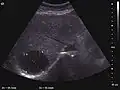

2D ultrasound, Doppler ultrasound and especially CEUS can play an important role in pretherapeutic staging, particularly when sectional imaging investigations (CT, MRI) provide uncertain results or are contraindicated. During the interventional procedure, ultrasound allows guidance of the needle into the tumor. CEUS allows guidance in areas of viable tissue and avoids intratumoral necrotic areas. CEUS also allows assessment of therapeutic effect immediately post-procedure (with the possibility of reintervention in case of partial response) . To accurately assess the effectiveness of treatment it is mandatory to compare the tumor diameter before therapy with the ablation area. The volume of damaged tissue must be higher than the initial tumor volume. CEUS appearance is that of central nonenhanced area showing a peripheral homogeneous hyperenhanced rim due to post-procedure inflammation. 24 hours after the procedure the inflammatory peripheral rim is thinning and the necrotic area appears larger than at the previous examination. Thus, a possible residual tumor may appear more evident. Residual tumor has poorly defined edges, irregular shape, and the tumor diameter is unchanged. Residual tumor tissue is evidenced at the periphery of the tumor as an eccentric area behaving as the original tumor at CEUS examination, with arterial hyperenhancement and portal and late wash-out. Ultrasound examination 24 hours after the procedure, including CEUS, can show apart from the character of the lesion any potential post-intervention complications (e.g. active bleeding).

In the first days after RFA both CEUS and spiral CT have low sensitivity in assessing therapeutic efficacy. CT sensitivity 24 hours post-therapy is reported to be even lower than CEUS. Difficulties in CEUS examination result from post-lesion hyperemia, presence of intratumoral air, ultrasound limitations (too deep lesion or the presence of fatty liver) or lack of patient's cooperation (immediately after therapy). For this reasons contrast imaging (CT or CEUS) control should be performed one month after ablation to confirm the result of the therapy.

Local recurrence is defined as recurrence of a hyperenhanced area at tumor periphery in the arterial phase, with portal and late wash-out. Sometimes, especially for HCC treated by alcoholization (PEI) hyperenhanced septa or vessels can be shown inside the lesion.